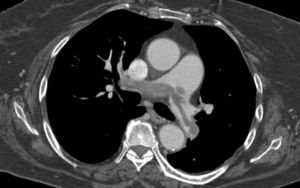

Estudo imagiológicoAs imagens de TCMD foram adquiridas na direção craniocaudal (colimação de 1,25mm), permitindo uma avaliação precisa das artérias pulmonares principais, lobares, segmentares e subsegmentares, ao nível dos lobos inferiores, médios e superiores.

Para definir o índice de obstrução na TCMD, a árvore arterial de cada pulmão foi considerada como tendo 10 artérias segmentares (3 para os lobos superiores, 2 para o lobo médio e língula e 5 para os lobos inferiores), atribuindo-se 1 ponto a cada artéria obstruída12. No caso das embolias que envolviam uma artéria pulmonar principal ou lobar, atribuiu-se uma pontuação referente ao número de artérias segmentares não vascularizadas.

Para fornecer informações adicionais acerca da perfusão distal residual, um fator de ponderação foi atribuído a cada valor dependendo do grau de obstrução vascular presente (obstrução total=2 pontos) (Tabela 1), obtendo-se um score máximo possível de 40 pontos.

Para além da avaliação da carga embólica na TCMD, foram efetuadas medições quantitativas dos diâmetros das estruturas vasculares (VCS e VA) e cardíacas (VD, VE, ratio VD/VE; SC, AP, Ao, ratio Ap/Ao) relacionadas com a árvore pulmonar. O desvio do SIV e o refluxo de contraste na veia cava inferior (VCI) foram avaliados qualitativamente, de forma a definir os sinais de DVD (Figuras 2-5).